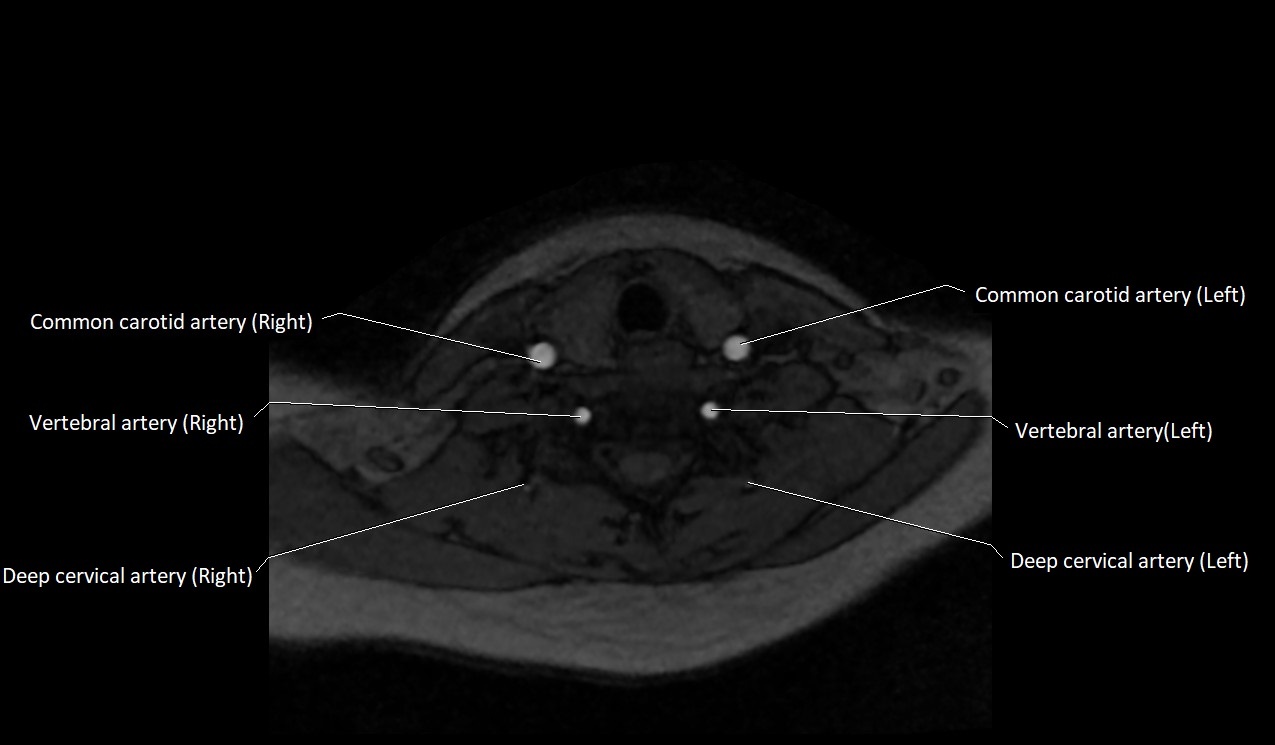

MRI images

image